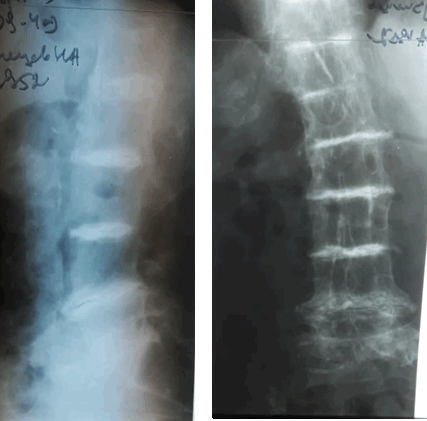

При рентгенологическом исследовании поясничного отдела позвоночника в двух проекциях на фоне диффузного остеопороза определялось резкое сужение и обызвествление межпозвонковых дисков, выраженный субхондральный остеосклероз тел позвонков, синдесмофиты, что весьма характерно для охроноза (рис. 2).

Рис. 2. Рентгенограммы поясничного отдела позвоночника пациента Н.

Высота межпозвонковых дисков резко снижена, отмечается их обызвествление. Диффузный остеопороз тел позвонков